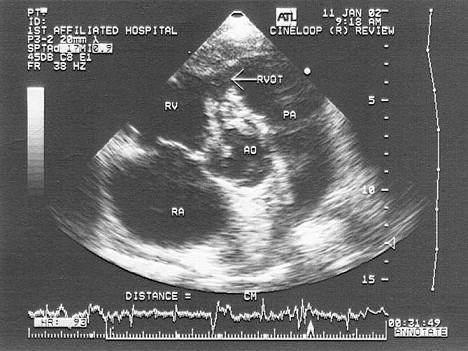

患者反复发热,原有先心病史,该病例最有可能诊断?(?)A.室缺并感染性心内膜炎B.主动脉瓣脱垂C.窦瘤破裂D.右流狭窄E.肺动脉瓣狭窄

问题 患者反复发热,原有先心病史,该病例最有可能诊断?(?)

选项 A.室缺并感染性心内膜炎 B.主动脉瓣脱垂 C.窦瘤破裂 D.右流狭窄 E.肺动脉瓣狭窄

答案 A